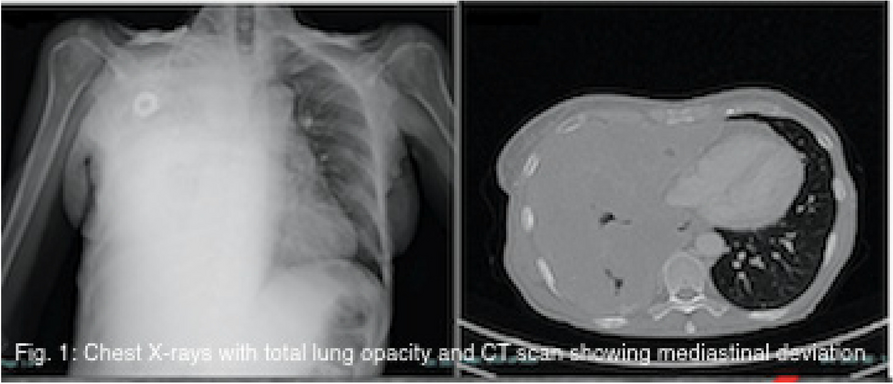

A few hours after the admission in ICU he reported a blunt abdominal pain, mainly on the right side, nausea and the exams showed increased amylase levels, urologists excluded any surgical involvement of pancreatic tissue and suspected a transient sphincter of Oddi dysfunction [3]. After one night in ICU he was transferred to the urology ward due to his clinical stability, even though Amylase peaked at 2340 U/l. Two days later abdominal pain increased to severe, with characteristics of peritonism and increased inflammatory markers. An abdomen-thorax CT scan revealed acute pancreatitis (AP) (Figure 1) and he was transferred to ICU. He started a standard treatment for acute pancreatitis and antibiotic therapy [4].

Fig. 1 (abstract A21).

See text for description